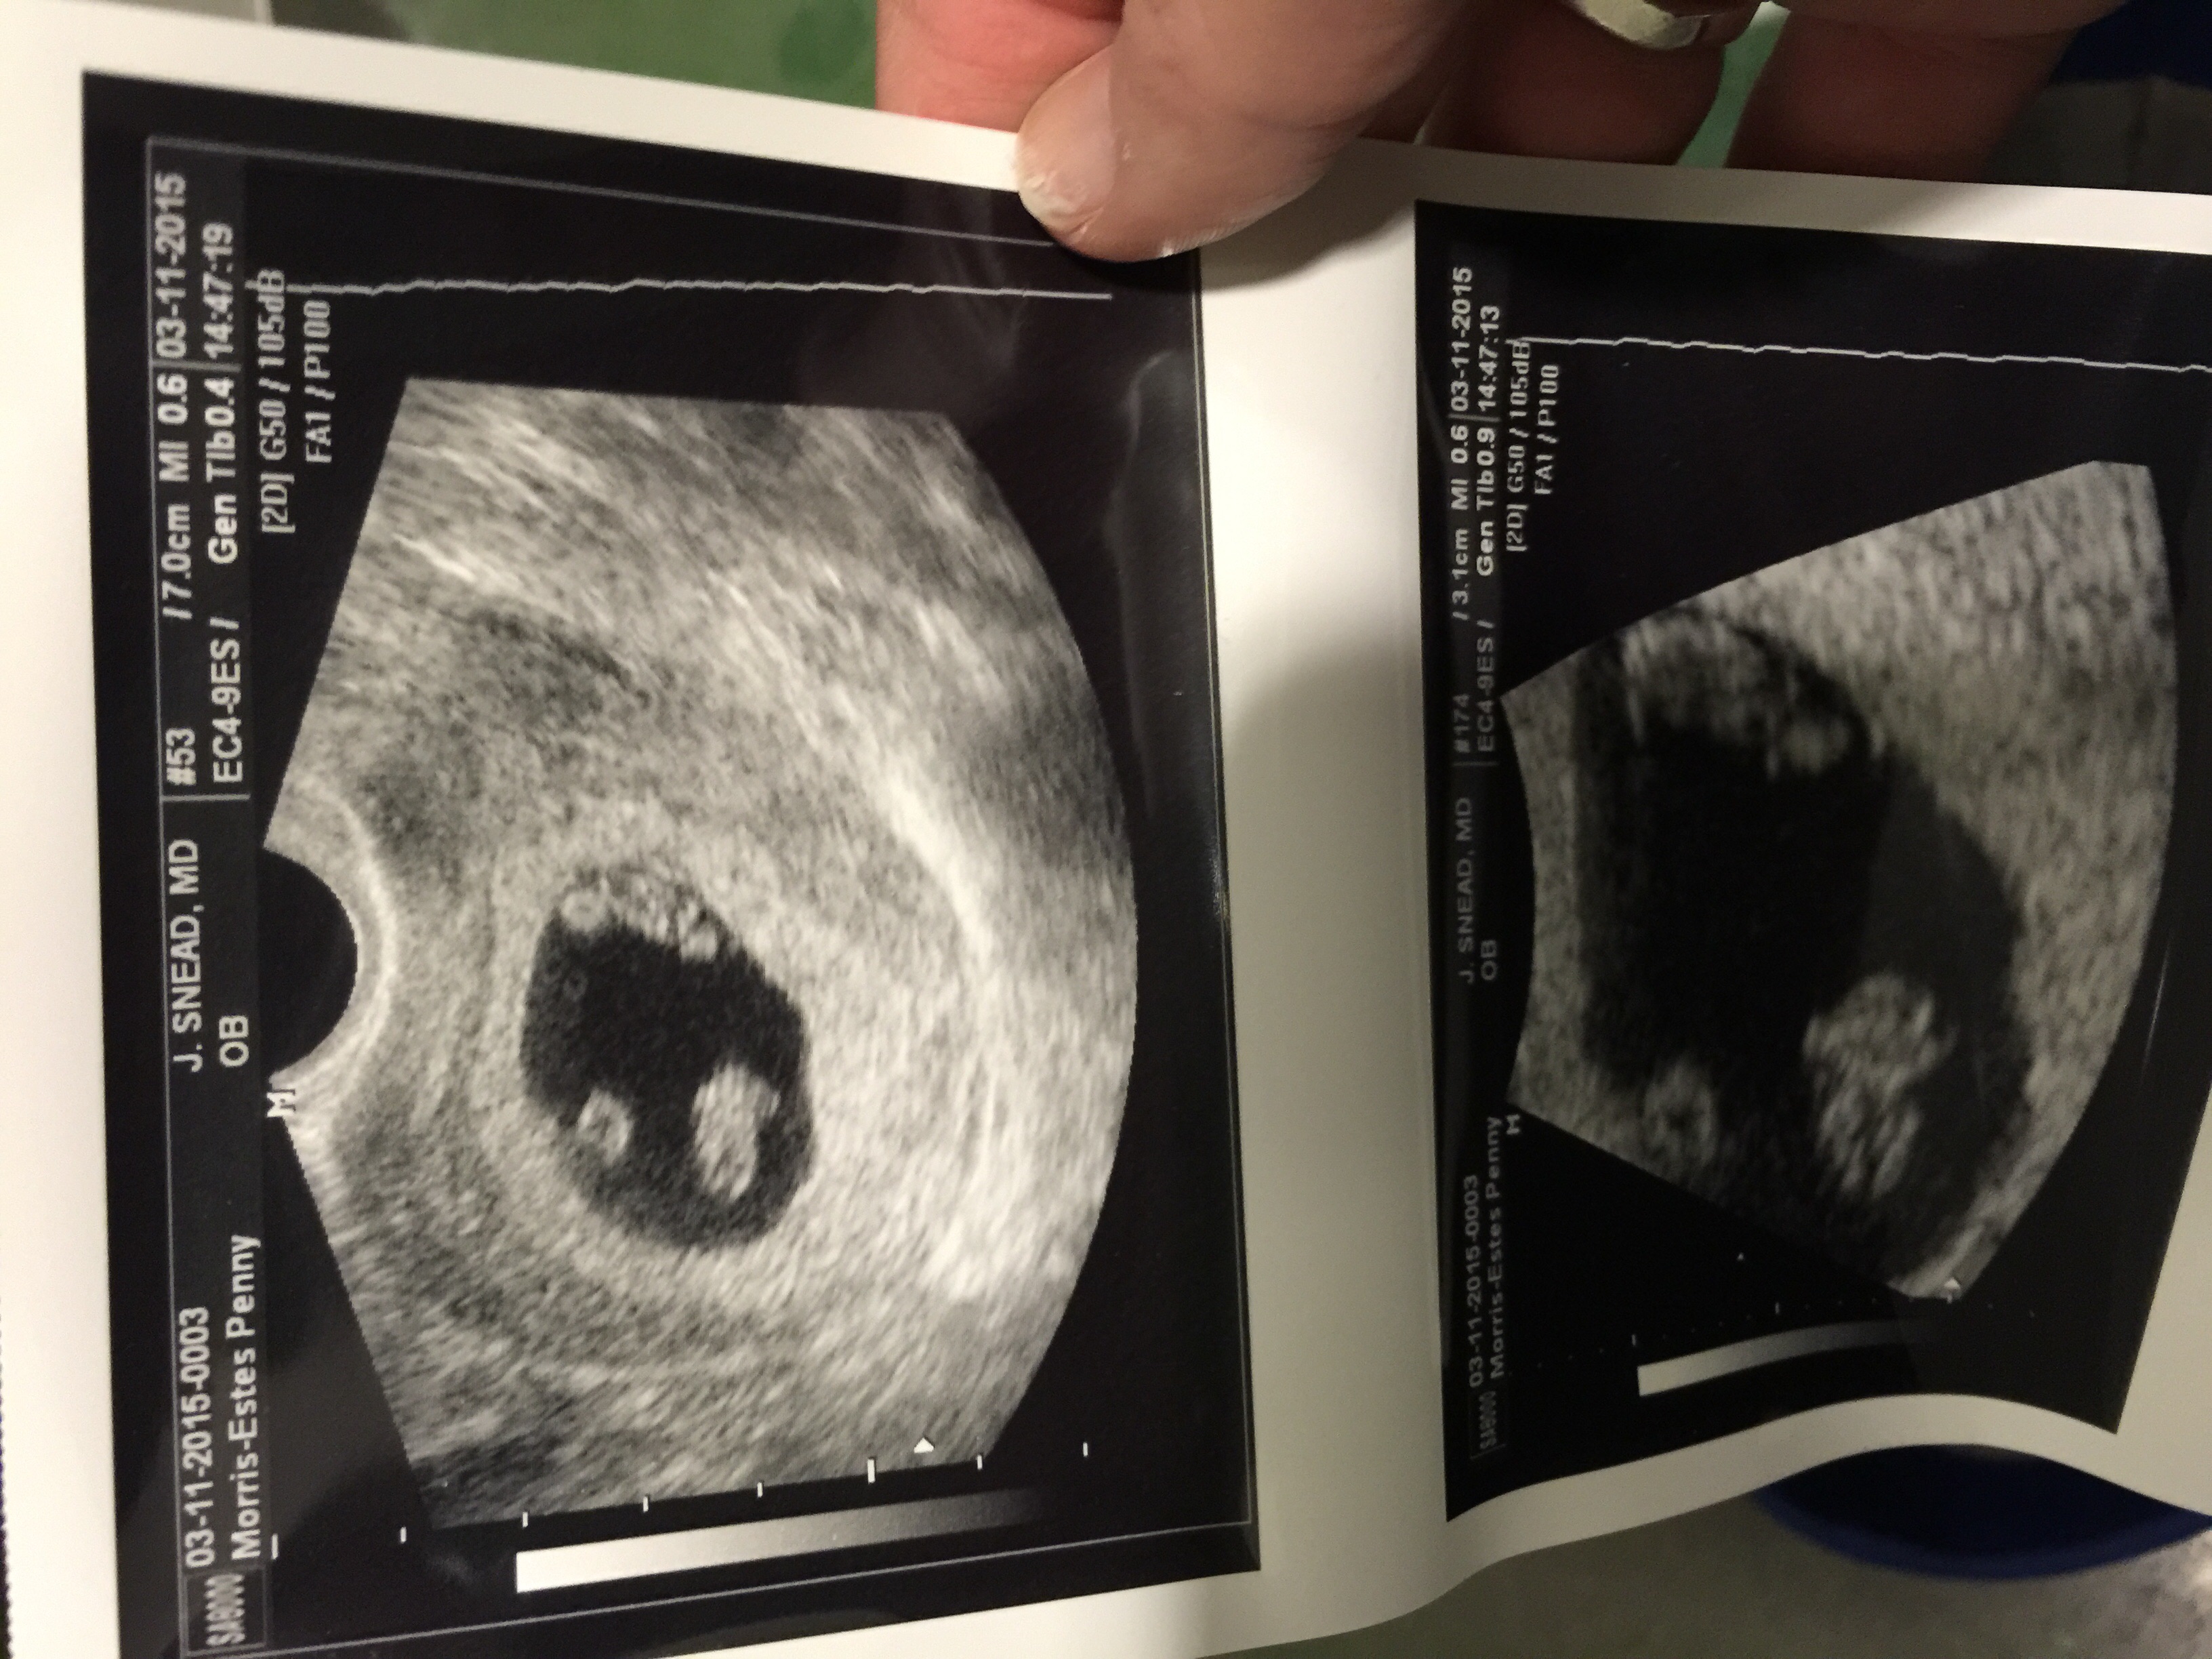

Baby Walton today (3/11) at 9w4d gestational age is +1 day! He even stretched his arm out during the U/S and we saw the heartbeat!! HR is 162 bpm so in love with this tiny thing!!